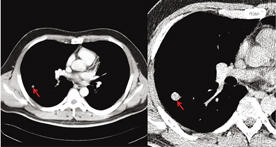

Case 1. Metastatic squamouse cell carcinoma.iŽÊ^‚Pj

‰E‘å”]”玿‚Ɛ‘Ž¿‚Ì‹«ŠE•”ˆÊ•t‹ß‚ÉMRI T1Gd‚Åring-enhance‚ð”F‚ß(a)CMRI T2‚ł͎îᇂƂ»‚ÌŽüˆÍC”’Ž¿—̈æ‚Éenhance‚ð”F‚ß‚é(bjD

Šp‰»×–E‚ƂȂª‚ê‚ð‚à‚Âcluster‚ð”F‚ß‚éDŒÂX‚̍זE‚ÍŠj‚̑召•s“¯CŠjƒNƒƒ}ƒ`ƒ“‚Ì‘‰Á‚ð”F‚ß‚é(djD

‰óŽ€‚𔺂¢CŠp‰»‚ðŽŠ‚·ˆÙŒ^×–E‚ð”F‚ß‚éD×–E‘œ‚ƈê’v‚·‚鏊Œ©‚Å‚ ‚éDŠp‰»Œ^G•œã”çŠà‚Å‚ ‚éD

‡@×–Ef’f‚Í”äŠr“I—eˆÕ‚Å‚ ‚邪C‚Ü‚ê‚ÉäP‰èŽî‚Æ–¢•ª‰»Šà‚̊ӕʂɋꗶ‚·‚éê‡‚à‚ ‚éDŠù‰—ð‚̃`ƒFƒbƒN‚Í–Y‚ꂞ‚ɍs‚€‚ׂ«‚Å‚ ‚éD‡A”]ŽÀŽ¿“à‚ɂł«‚œ“]ˆÚ«Šà‚́C”玿‚Ɛ‘Ž¿‚Ì‹«ŠE•”ˆÊ•t‹ß”­¶‚ª‘œ‚¢D‚Ü‚œ”]•\–ʂɔ­¶‚µ‚œê‡‚́C‘–ŒŽî‚Æ“¯—l ˆ³”r«‘B‚ªŠÏŽ@‚³‚ê‚éD‡B”]ŽÀŽ¿‚É“]ˆÚ‚µ‚â‚·‚¢‚͔̂xŠàCtŠàCÁ‰»ŠíŠàC“î–Œ“]ˆÚ‚Í“ûŠàC”xŠàCˆ««•FŽîC”’ŒŒ•a‚Ȃǂł ‚éD

ŽÊ^‚P Case 1D

Metastatic squamouse cell carcinoma.

ò_ MRI T1 Gd. ò` MRI T2.

òa HE x200. òb Pap x400